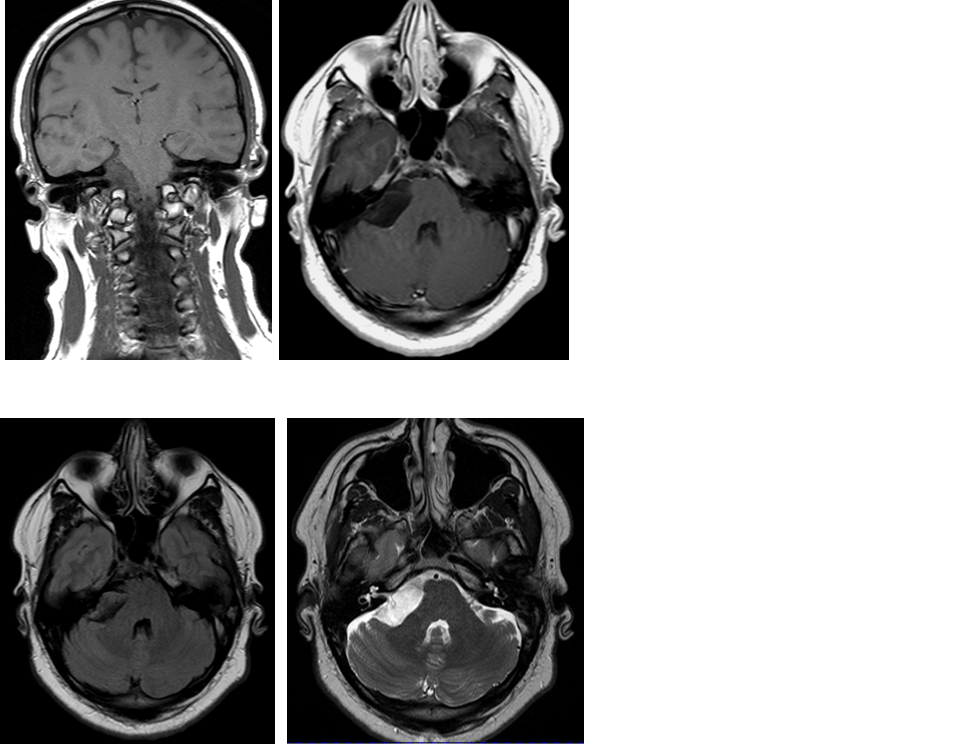

Tim 4G神经系统临床应用

Tim 4G高密度一体化头颈线圈提供高分辨率头部成像,更多的线圈单元数支持更高的iPAT并行采集因子,有利于减少EPI序列的磁敏感伪影。

CASE 2:多发硬化 MS